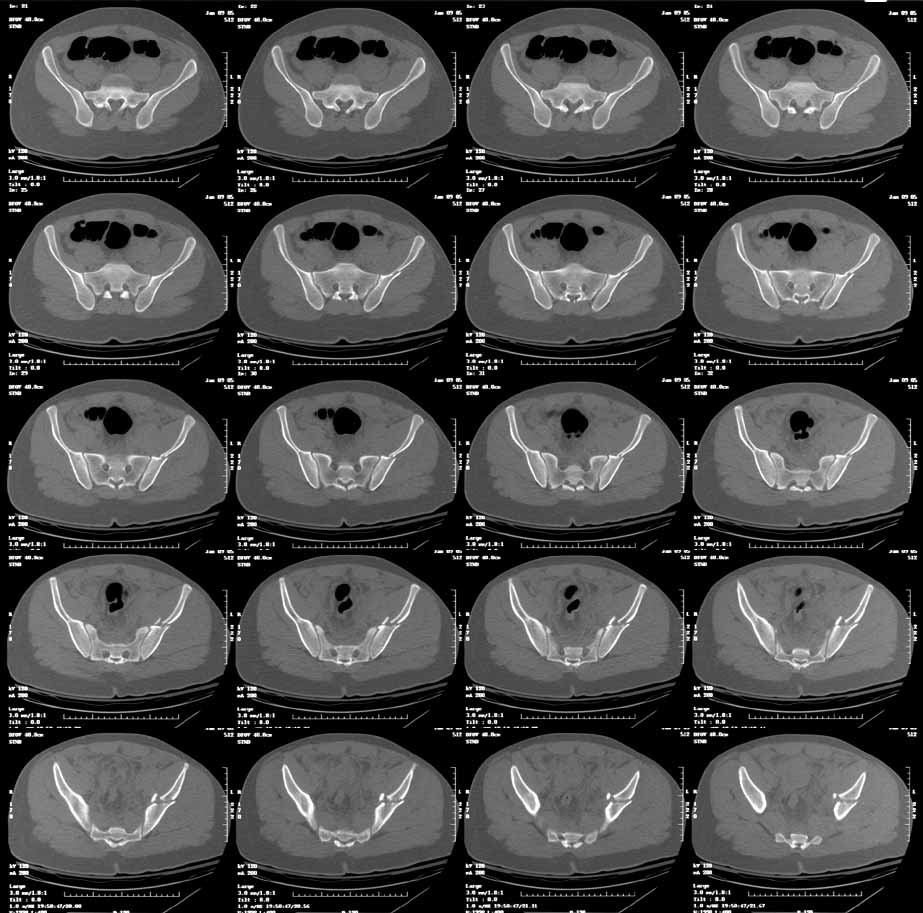

This is an 18 yo male involved in an MVA 2 days ago. Isolated injury other than some rib fxs. I had trouble interpreting the xrays, but the CT shows a both column fracture with secondary congruence (I think). The plain films show significant gapping of the anterior column, but the CT shows fairly little at the dome.

You'll notice by CT that there is an intact labral "hinge" which usually indicates that these 2 dominant articular fragments will behave together intraop. But you'll still need to expose, clean, and clamp them before fixation. And your operative goal is to have the articular reduction be perfect on the postop CT...can you make this one better?

You'll notice that the anterior column is incomplete peripherally...this lends stability if you elect to treat him without surgery, and indicates an osteotomy at the iliac crest to complete the fracture and allow its mobilization for cleaning and reduction, should you choose surgery.